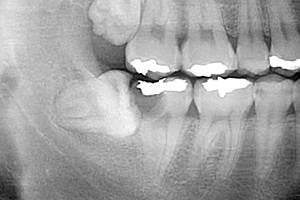

下の親知らずが横向きに生えています。手前の歯を押して、手前の歯がいたんでいる状態です。